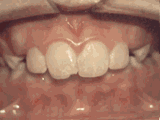

Overbite: Protruding front teeth

At age 10, patient had a big overbite with the top teeth protruding beyond the bottom. She had two phases of treatment. The first helped her jaws to grow more harmoniously and the second aligned her teeth and bite. At age 13, she was proudly displaying her new smile.